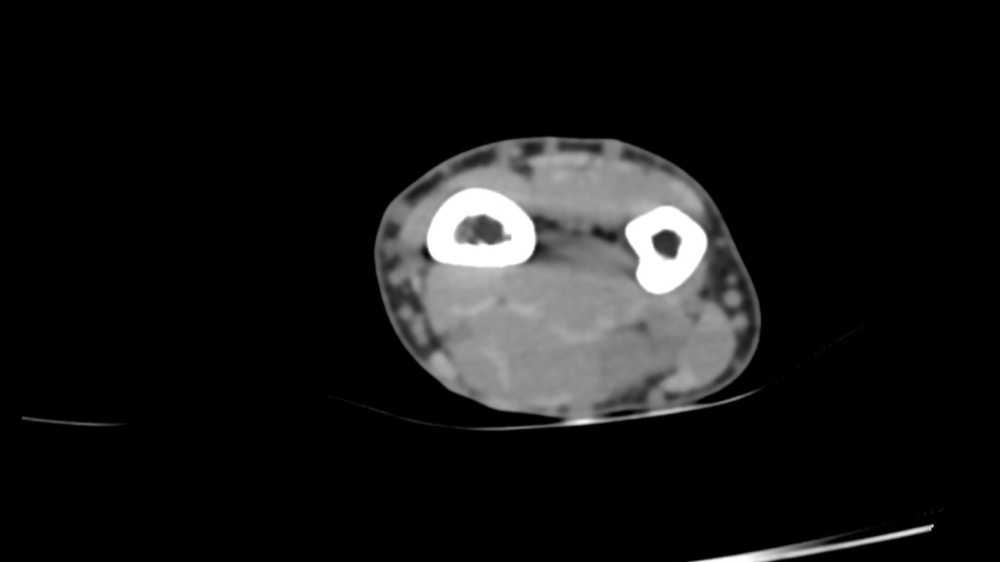

Bone Club

Thomas Leclerc 23/03/2022